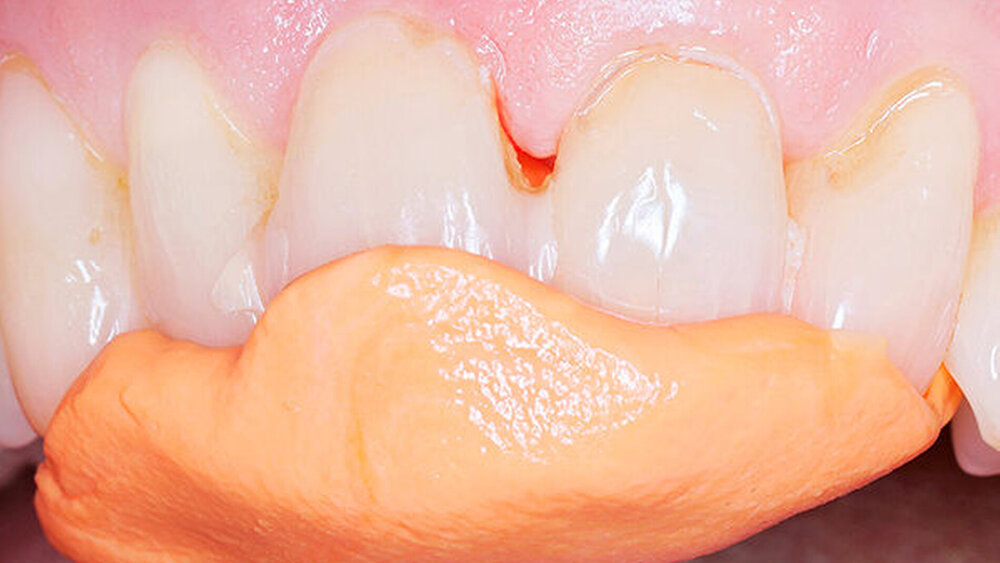

In welchen klinischen Anwendungen bietet das Implantat Vorteile?Hermann:Das neue CAMLOG PROGRESSIVE-LINE Implantat besticht durch sein innovatives parallel-konisches Makrodesign mit einem speziellen Gewinde, bei gleichzeitig bewährter Prothetikschnittstelle der Camlog-Linie. Dies bedeutet, dass in der chirurgischen Phase mit diesem Implantat eine zuverlässige Primärstabilität erzielt werden kann, speziell bei schwierigen anatomischen Voraussetzungen, wie z. B. bei der Sofortimplantation, bei reduzierter Kieferkammbreite oder konkav verlaufenden Alveoloarkämmen sowie bei weichem Knochen im Oberkiefer. Aufgrund des krestalen Verankerungsgewindes sehen wir zudem einen Vorteil bei der Platzierung des Implantats im Zusammenhang mit einer simultanen, offenen Sinusbodenelevation bei stark reduzierter Restknochenhöhe (2–3 mm). Auch einzeitige Verfahren lassen sich einfacher durchführen. Denn auch im kompromittierten Knochen erreicht das Implantat eine hohe vorhersagbare Primärstabilität.

Sind dann auch eher Sofortversorgungsprotkolle umzusetzen?Hermann:Die erzielte Primärstabilität ist in den meisten Fällen so hoch, dass eine sofortige provisorische Versorgung/Belastung möglich ist. Somit können wir unseren Patienten effiziente Behandlungsabläufe anbieten. Die Effizienz zeigt sich beispielsweise auch bei der Reduktion der Bohrschritte durch ein flexibles Bohrprotokoll. Gerade im weichen Knochen benötigen wir meist nur drei Bohrschritte bis zur Insertion des Implantats und erzielten eine exzellente Primärstabilität durch eine geringere Aufbereitung des Implantatbetts. Auf den zusätzlichen Einsatz nicht-ablativer Techniken (Osteotome) kann häufig verzichtet werden. Ein Teil der 80 von uns gesetzten PROGRES ‧ SIVE- ‧ LINE Implantate befindet sich bereits in der prothetischen Nachkontrolle. Das klinische und prothetische Outcome ist hervorragend. Es gibt weder chirurgische Komplikationen noch Probleme bei der Einheilung, und die prothetische Versorgung funktioniert perfekt.